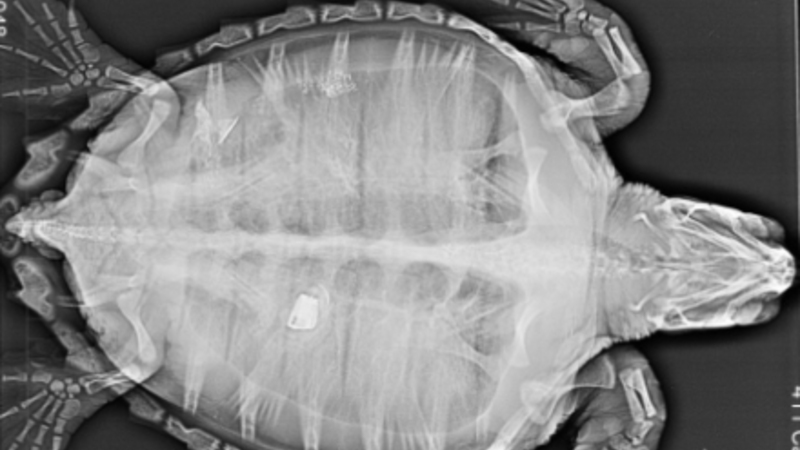

Dyrlægerne hos akvariet gjorde store øjne, da de gav skildpadden en ultralydsscanning og så, hvad der lå og rumsterede i dens tarm.

Det lille dyr havde nemlig gumlet et stykke af en lighter i sig, og det kom der et noget spøjst røntgenfotografi ud af:

Ikke ligefrem et typisk røntgenbillede

Lægerne var selvfølgelig nervøse for, at fyrtøjet skulle gøre skade på padde, men heldigvis gik der ikke længe, før lighteren kom ud ganske naturligt:

Nederst i billedet kan man se det lille stykke lighter, som drillede padden